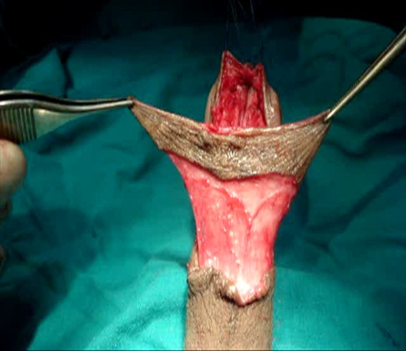

However, in the other 11 patients, who had been treated with transverse penile island flap and split glanuloplasty. Exposure was through a short transverse incision on the ventrum of the penis 0.5cm proximal to the coronal sulcus, & degloving of the ventral aspect deep to the dartos fascia. Ventral stricturotomy was carried out from the external meatus distally to the healthy penile urethra & glanular wings were created. Elevation of the transverse penile island flap was carried according to the length and caliber of the urethra needed as in Figure S2. A suitable silicone urethral catheter was inserted. The flap was rotated 90 degrees to be vertically oriented as in Figure S3A. Working from the proximal end, a submucosal suture with 5-0 Vicryl was taken to complete the urethral closure, another layer of dartous for augmentation of the suture, closure of the coronal incision and closure of the glanular wing with 5-0 Vicryl subcuticular suture. The incision at the coronal sulcus was approximated with a fine sub-cuticular suture. A suitable silicone urethral catheter was inserted for 3 weeks Figure S4.

Figure S4 Glanular shape after transverse penile island flap with glans cap technique.